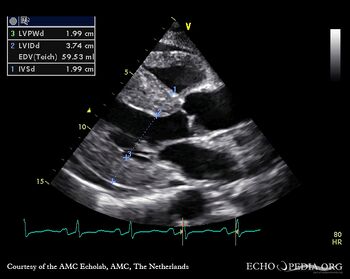

| Amyloidosis

| Courtesy of: AMC Echolab, AMC, The Netherlands

M-Mode through left ventricle